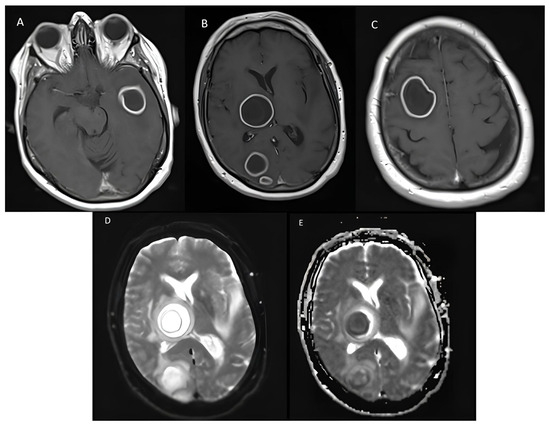

2. Detailed Case Description